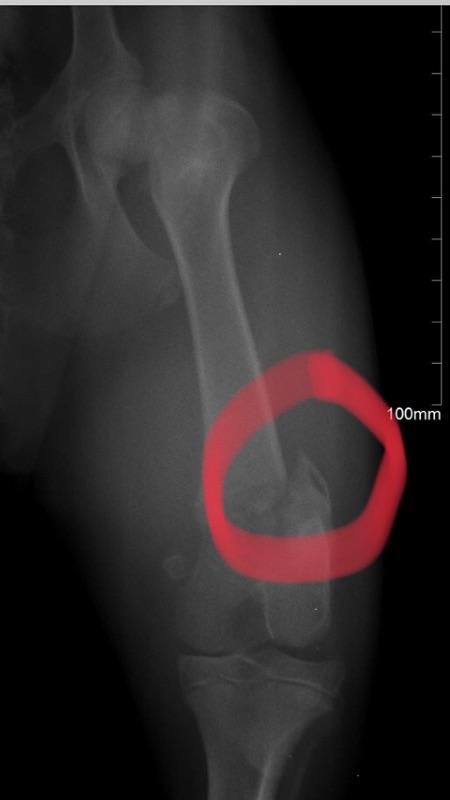

My puppy was hurt at a boarding place. The vet we took him to said he needed surgery, the owner wanted a second opinion and the other vet said it would heal on it's own with proper rest. Can the fractures heal on it's own?

They can definitely heal on their own and they heal especially well with puppies. However, it may heal at an angle, which can cause a life-long limp and issues with arthritis. This particular fracture involves the growth plate, which can increase the possibility that it won't heal correctly. The advantage of surgery is that the fracture can be aligned appropriately, which will shorten healing time and reduce chances of future complications. This would not be an easy surgery though and would likely require an orthopedic specialist to do it; which can get quite expensive. If you want to pursue surgery, then it's best to ask your veterinarian for a referral to an orthopedic specialist. Otherwise it's possible for it to heal fine with casting/splinting and time. I hope that helps and Ice gets better soon.